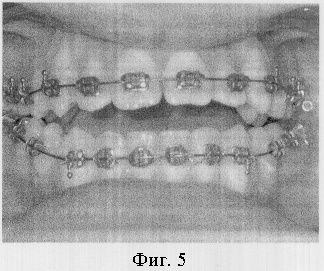

Пример 1. Пациент Б.С., 17 лет. Диагноз: дистопия верхних и нижних клыков (фиг.4). Проводилось ортодонтическое лечение с использованием брекет-системы. Клыки установлены в зубной ряд, но при этом получена значительная протрузия передних зубов и значительная вертикальная межрезцовая щель (фиг.5).

Под местной анестезией проведена остеотомия во всю толщу альвеолярных частей обеих челюстей над корнями передних зубов. Установлены стальные дуги 0,17×0,25 (паз брекета – 0,18) с реверсионными изгибами. Спустя неделю начаты активации реверсионных изгибов на дугах (фиг.6). Через 2,5 месяца после операции достигнут ортогнатический прикус (фиг.7).